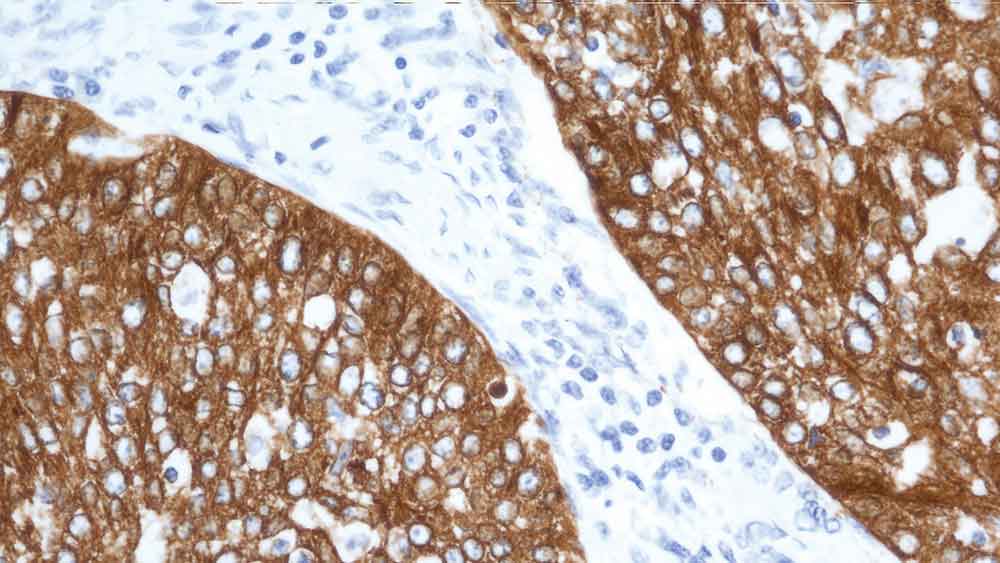

The smallest human cytokeratin filament protein (40 kD) has been identified as cytokeratin 19 and has been reported to be expressed in a large number of epithelial cell types, including many ductal and glandular epithelia.

Clone b170 produces a complex heterogeneous staining pattern in non-keratinizing squamous epithelia and hair follicles, with strong staining of the basal layer observed.

Cytokeratin 19 is recommended for the detection of specific antigens of interest in normal and neoplastic tissues, as an adjunct to conventional histopathology using non-immunologic histochemical stains.